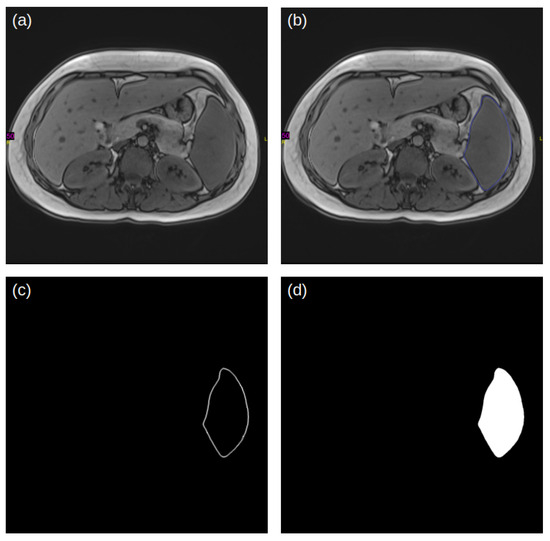

3.1. Modeling Pipeline